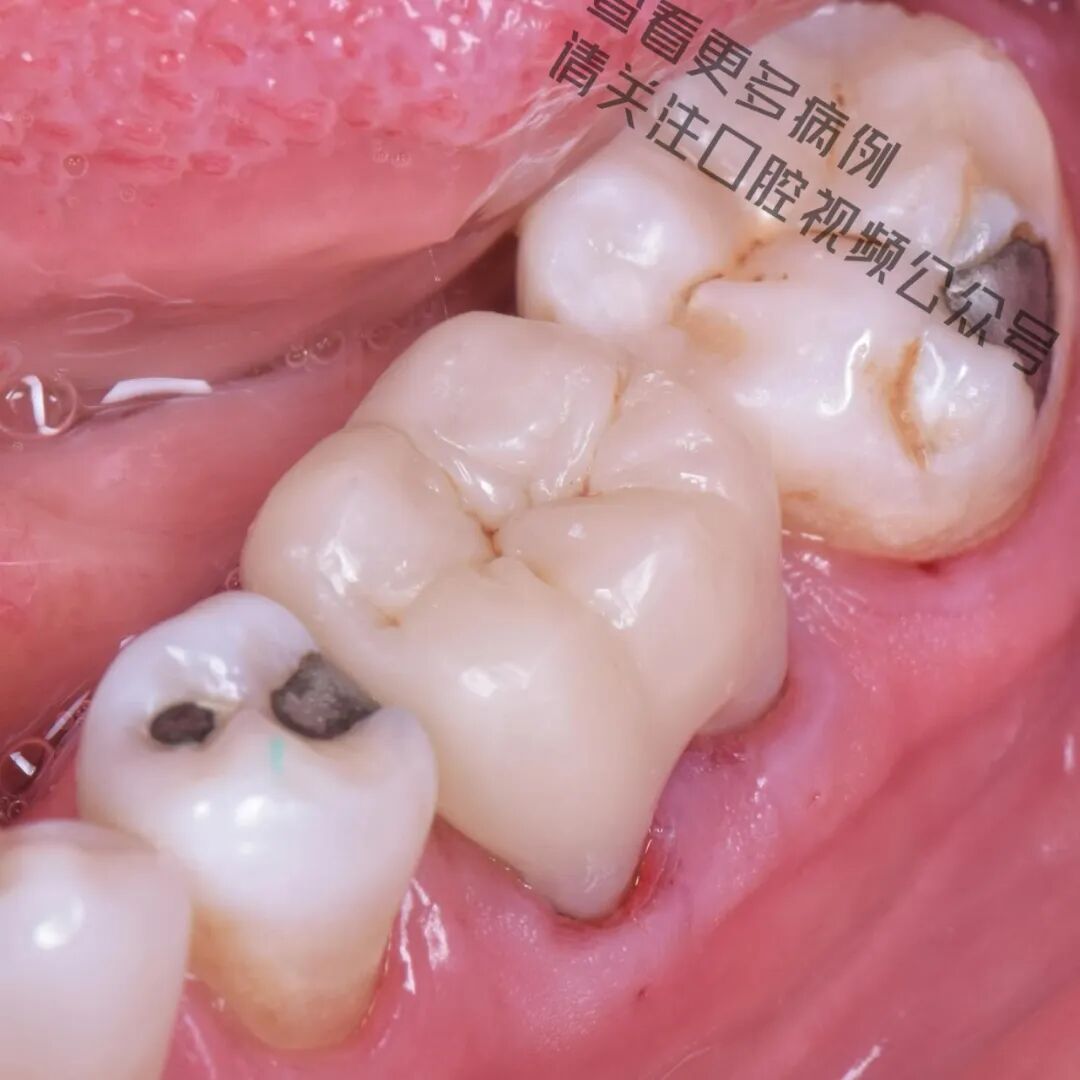

在这个病例中,仿生学理念(Biomimetics) 构成了整个治疗方案的核心基础。尽管牙齿结构已经严重脆弱化,但我们依然成功地恢复了其功能、强度与美观,完全遵循自然引导下的真正修复牙科原则。